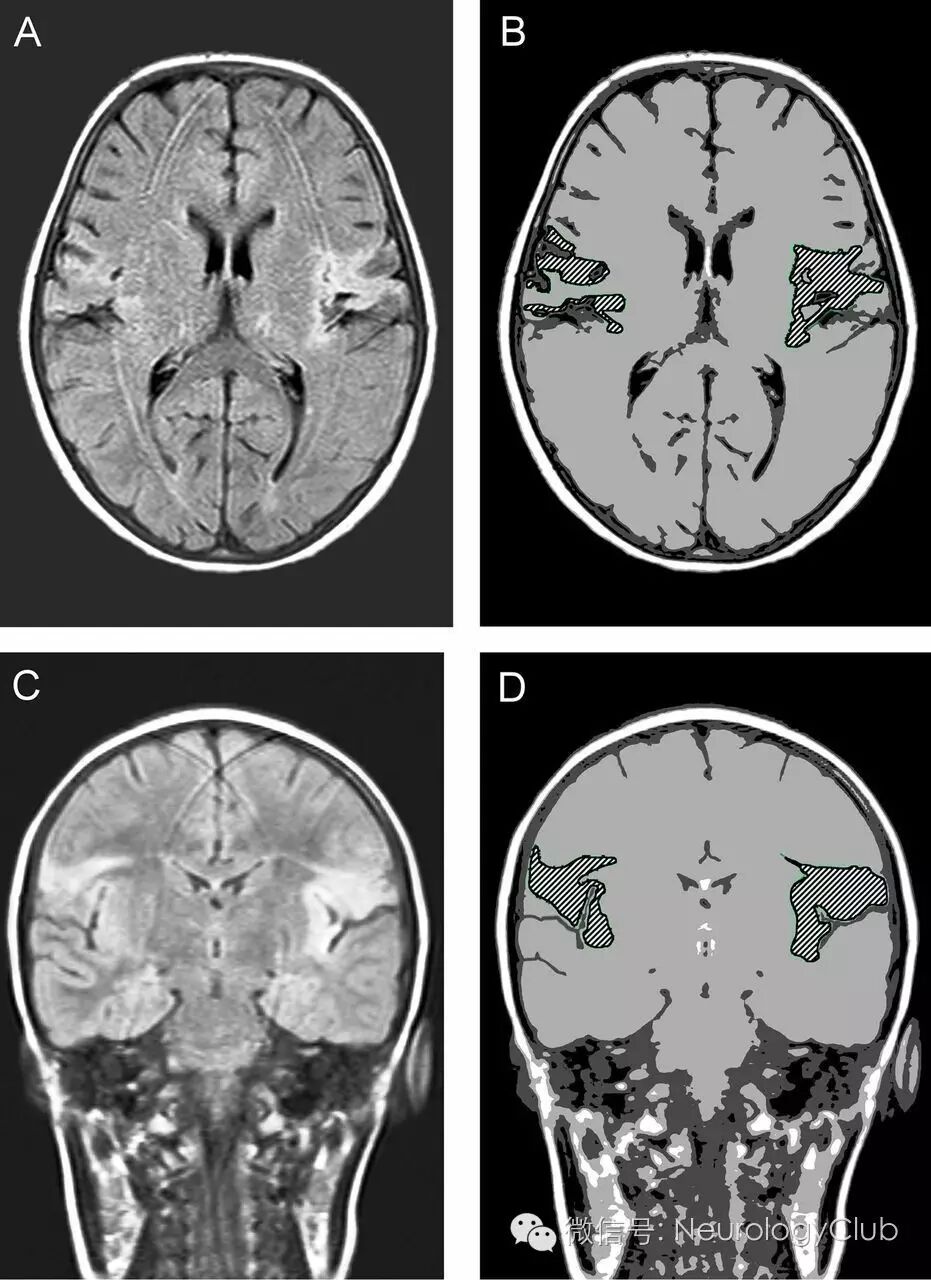

病例3:双侧外侧裂周梗死所致的FCMS

(图5:A-B:T2WI/FLAIR上可见双侧岛叶皮层高信号[箭];C:增强后右侧病灶强化,左侧无;D-E:DWI和ADC提示弥散受限;F:MRA正常)